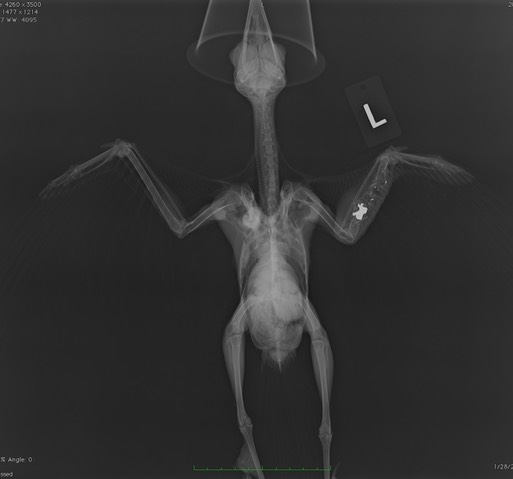

Red-tailed Hawk 19-556 was admitted on Thanksgiving with gunshot injuries: a fractured left ulna and a hairline fracture in the right humerus.